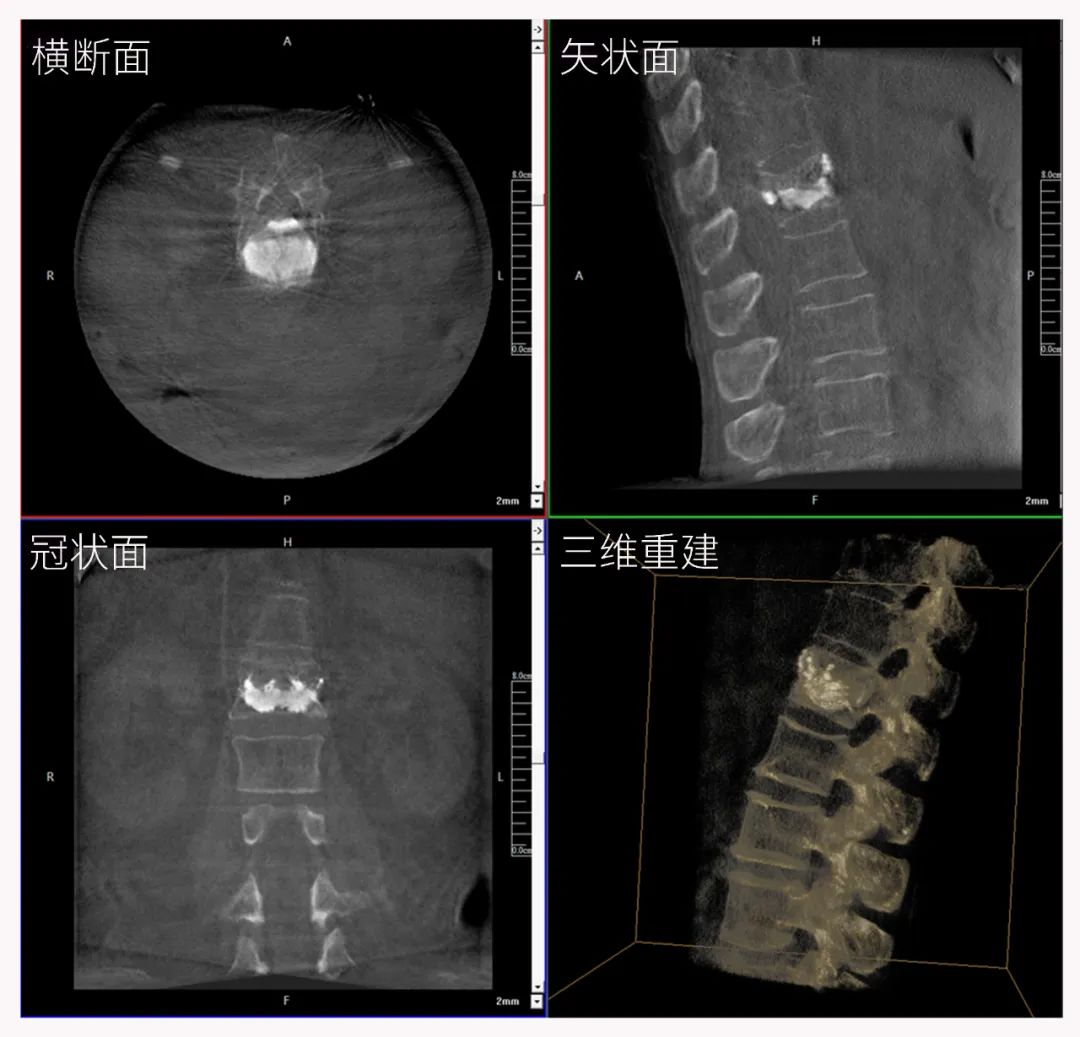

三維C形臂也被稱為“術(shù)中CT”,它具備二維C形臂的全部功能。此外,它還具備三維成像功能,三維C形臂旋轉(zhuǎn)采集多角度的二維投影數(shù)據(jù),再通過計(jì)算機(jī)進(jìn)行三維重建,能夠生成橫斷面、矢狀面、冠狀面斷層圖像以及三維立體圖像,提供更全面、更立體的解剖學(xué)信息。

三維“類CT”影像

在臨床使用中,三維C形臂能看到二維影像所觀察不到的信息:

二維C形臂提供的影像存在固有局限性,其成像原理是基于單一方位的投影,導(dǎo)致深部解剖結(jié)構(gòu)信息缺失,且容易受到骨骼和組織的重疊干擾,使得部分病灶難以清晰顯示,甚至被掩蓋。相比之下,三維C形臂通過三維重建技術(shù),可以獲得類似CT的斷層掃描圖像,從而解決了二維影像的重疊問題。

醫(yī)生能夠利用這些三維圖像,更直觀、更深入地分析病變,進(jìn)行全方位觀察,例如:精確評(píng)估骨折復(fù)位情況、清晰顯示內(nèi)植入物的位置及其與周圍組織的關(guān)系等。尤其在復(fù)雜骨折、脊柱手術(shù)、呼吸介入等臨床場(chǎng)景中,三維C形臂提供的詳細(xì)信息對(duì)手術(shù)導(dǎo)航和療效評(píng)估至關(guān)重要。